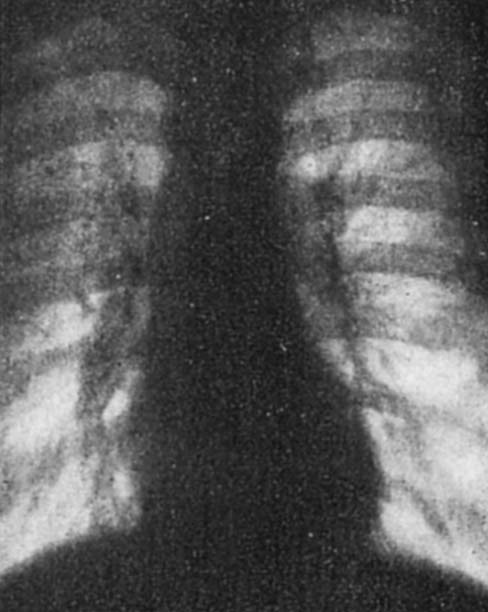

図1.(上)大動脈弁狭窄,(下) 僧帽弁閉鎖不全.弁膜症の典型的な心陰影[3].

さまざまな心疾患,特に弁膜症のX線所見が研究され,1912年にはGroede[2]が現在 mitral configuration, aortic configuration と呼ばれる各弁膜症に特徴的な心陰影の形態を報告しているが,1930年,Steel[3]が報告した弁膜症の総括論文は現在の知識をほぼ網羅している(図1).各心腔の個別評価には斜位像が有用であることはHolzknecht[4],Rieder[5]らの初期の教科書にもすでに記載されているが,1930年,O'Kaneら[6]が左斜位の重要性,Patterson[7]が食道との関係を指摘している.